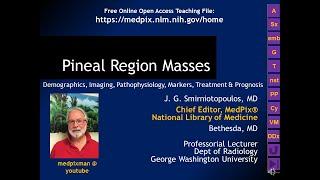

James Smirniotopoulos

Chest Radiology - Part 1, the Basics of the mediastinum & central structures

James Smirniotopoulos

2K

7,287

11 лет назад